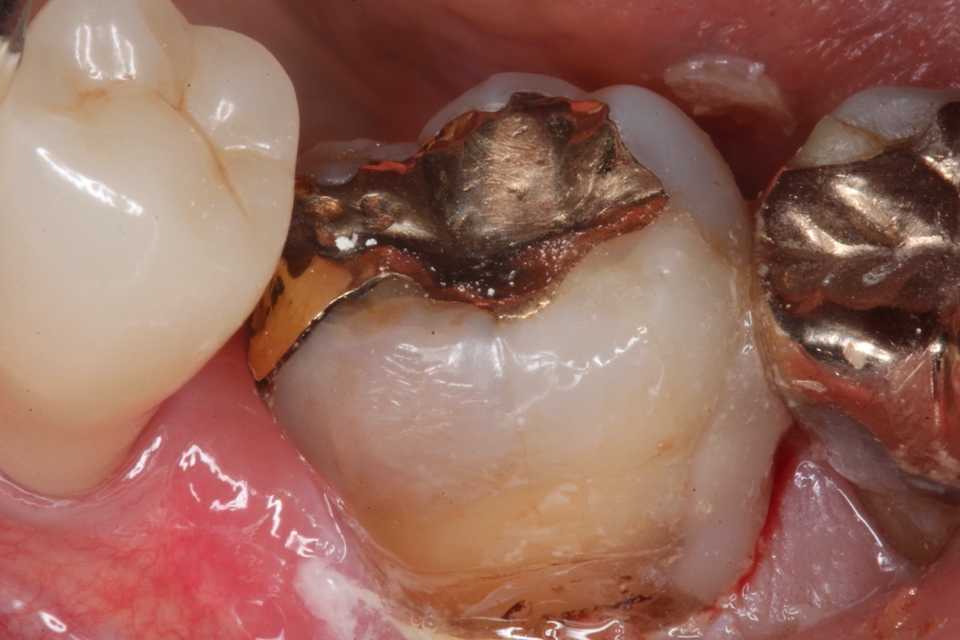

これが処置前の画像。亜鉛華ユージノールセメント貼付などの処置はしないで欲しいというのが本音。

セメントを削り取る時に露髄させたり、すでに露髄していて細菌を根管内に押し込んだりと増悪リスクが高いだけだ。前医はどうせ神経を取ってクラウンとか治療困難に付き抜歯してインプラントとか思っているので、セメントを剥がすことがあるなどとは最初から考えていないのだろう。